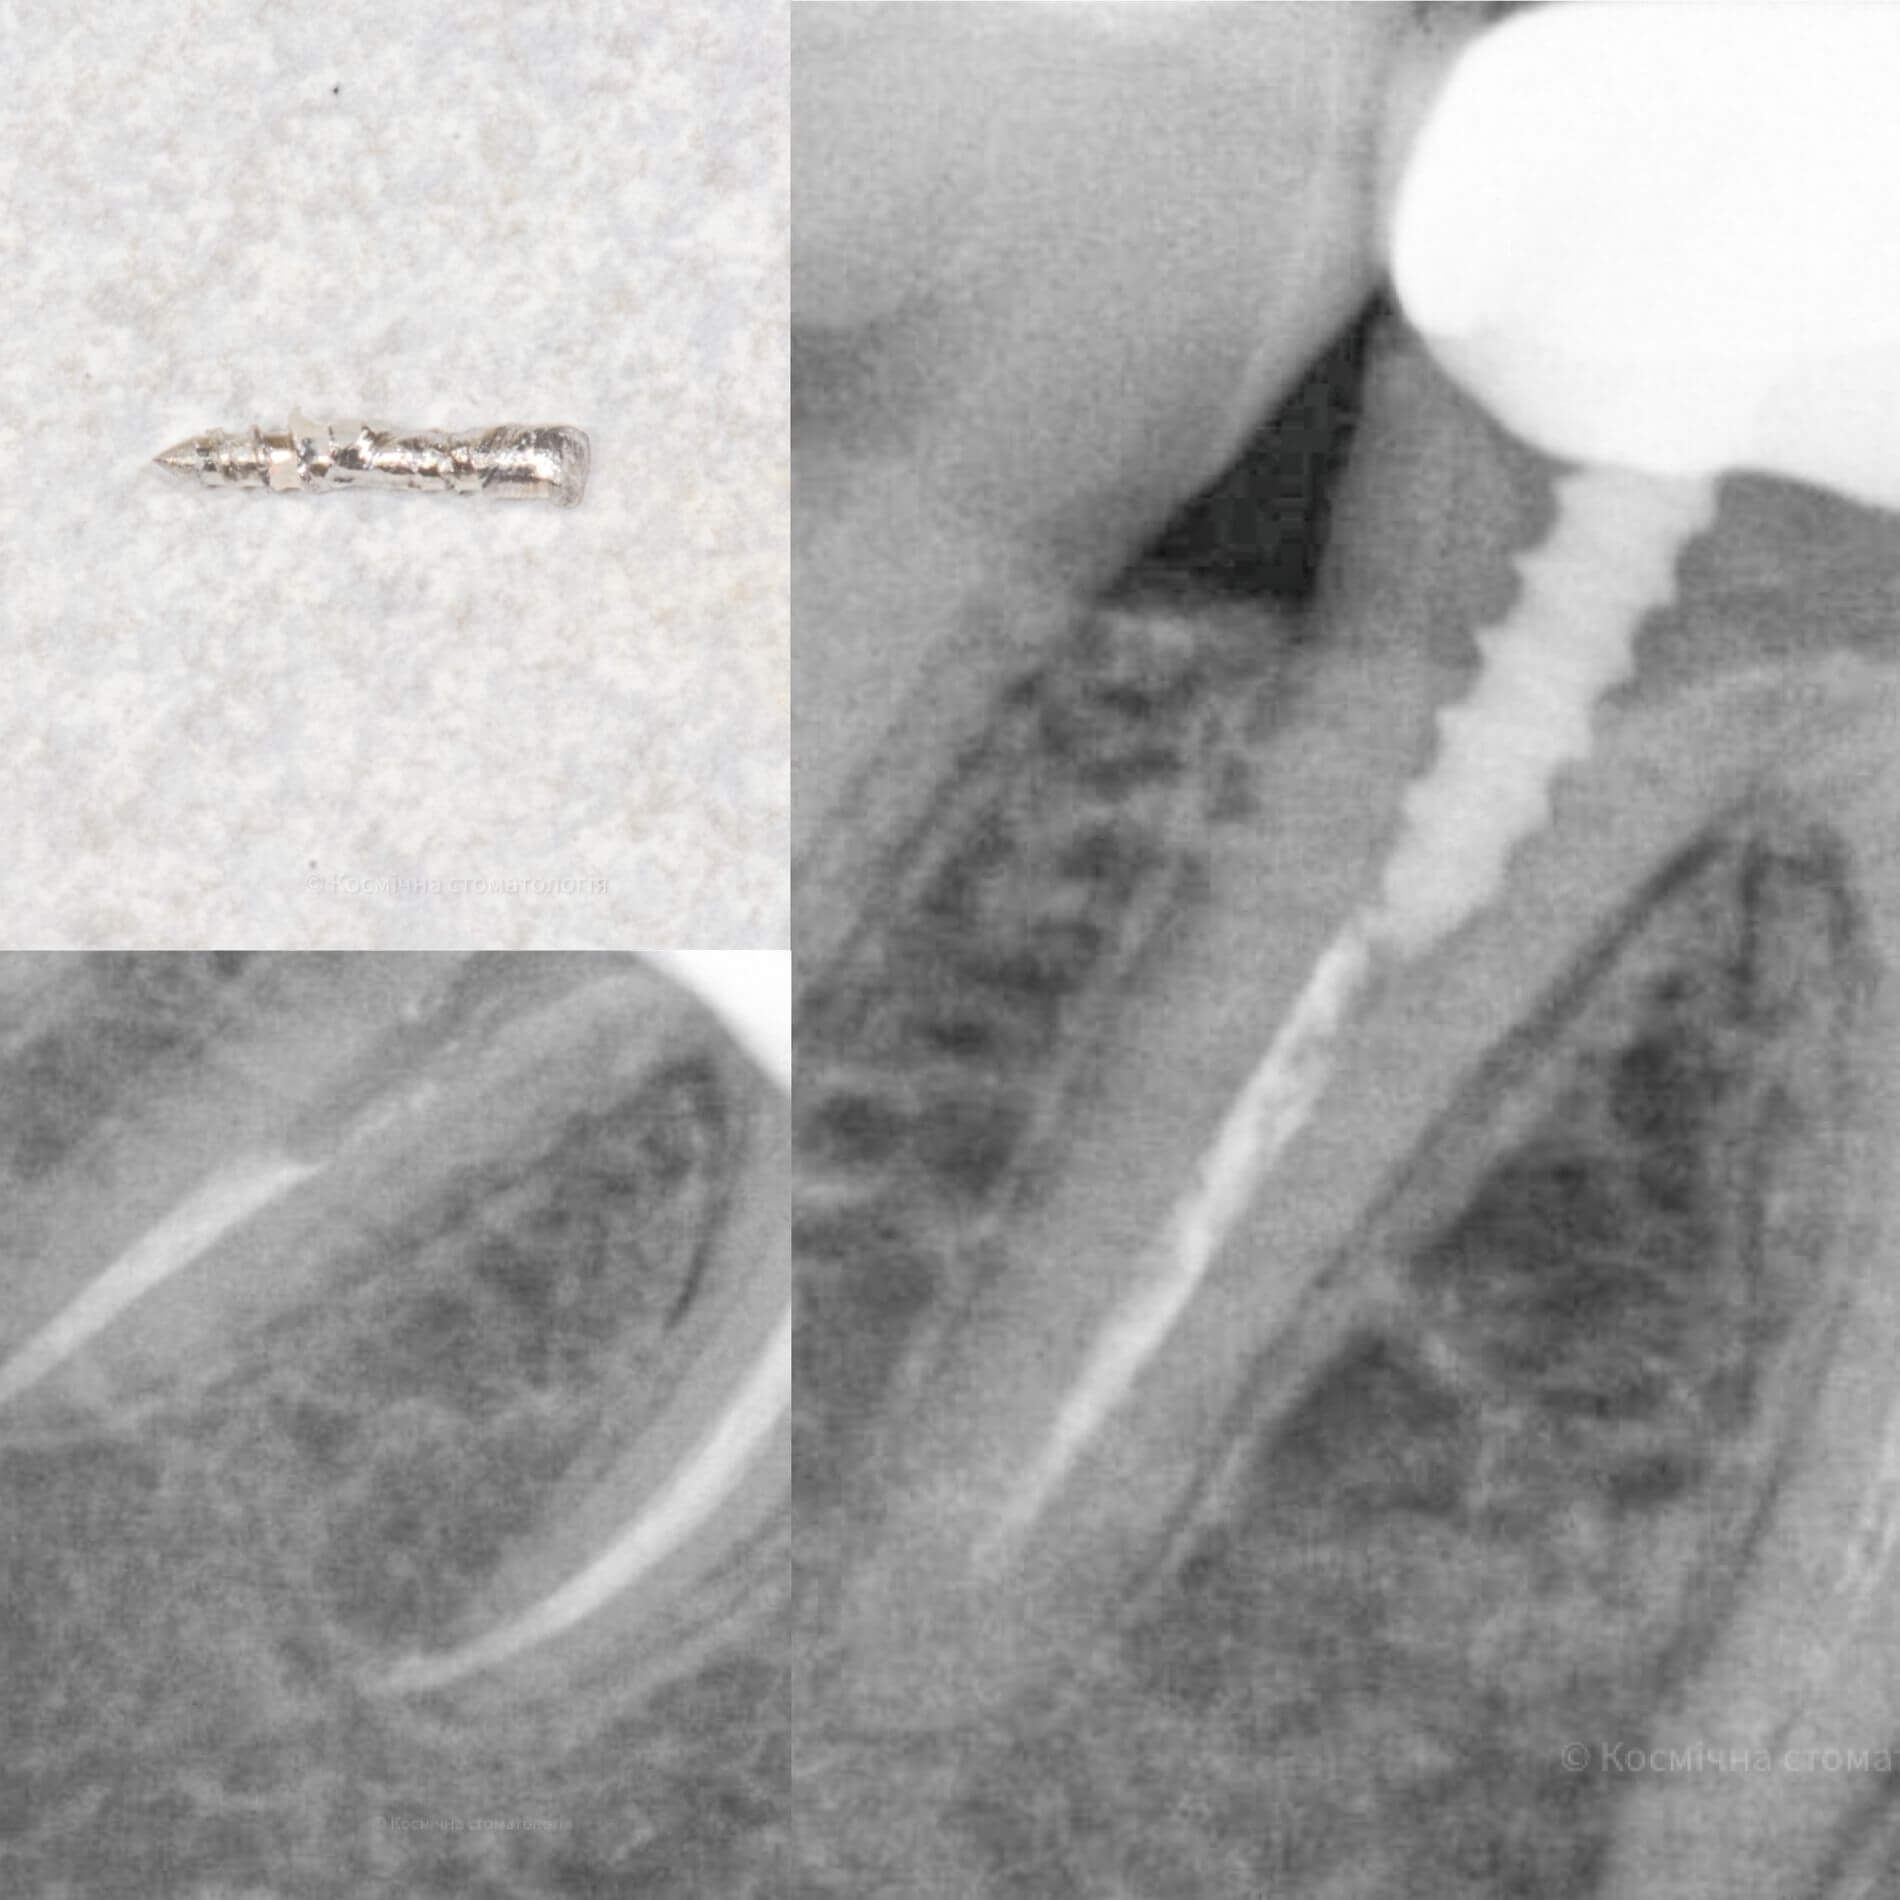

Мы уже говорили, качественное лечение зубных каналов – это довольно сложный и трудоемкий процесс, но с ним с легкостью справится наша космическая команда. Эта процедура затруднена отсутствием полноценного доступа к операционной полости, да еще зубные каналы часто искривлены и очень узкие, что делает невозможным визуальный контроль за проведением процедуры.

Но инновационные технологии и применение рентгенологического контроля выводят лечение каналов зуба во Львове специалистами Космической стоматологии Драганчука на новый межгалактический уровень.

- 3D пломбирование корневых каналов горячей гуттаперчей. Высокоэффективная техника, позволяющая заполнить все ответвления корневых каналов настолько плотно, чтобы достичь абсолютной герметизации. А значит, ни одна инфекция не сможет повторно поразить корневые каналы твоего зуба.

Чтобы провести процедуру лечения и пломбирования каналов, мы в космической стоматологии Драганчука используем оптическое увеличение с помощью микроскопа Carl Zeisse.

Он позволяет вывести изображение на большой экран и масштабировать его, чтобы наша космическая команда могла осуществить все необходимые манипуляции особенно скрупулезно. Благодаря такому оптическому контролю каждого этапа лечения, мы можем оценить его эффективность и предотвратить возникновение осложнений.